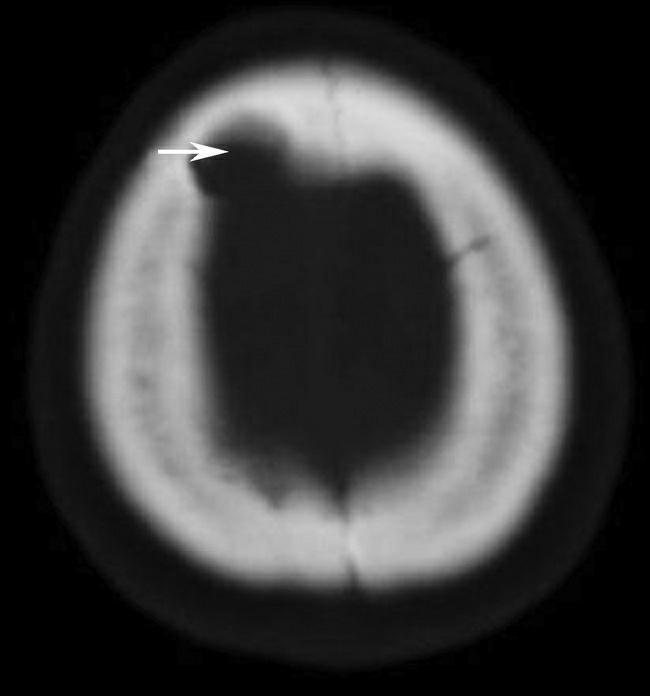

透明隔为两片膜状结构紧贴形成,之间有潜在腔隙,如扩大则形成透明隔腔,内含脑脊液样液体,称透明隔间腔或第五脑室,为正常变异(图1-2-37)。发育因素可导致双侧侧脑室的大小不对称(图1-2-38),一般无临床意义,但是需注意与病理性侧脑室不对称相鉴别(图1-2-39)。发育性因素导致的侧脑室不对称,脑实质及脑室内均无病变,且由大脑镰、透明隔等组成的中线结构无偏移。

图1-2-38 双侧侧脑室发育不对称

图1-2-39 病理性因素导致的双侧侧脑室不对称

A.右侧大脑半球转移瘤瘤周水肿(☆)引发的占位效应致右侧侧脑室明显受压变形、变小(箭),透明隔向左侧移位(箭头);B.左侧侧脑室旁陈旧性脑梗死、脑软化(☆),病灶体积缩小引发的负占位效应致左侧侧脑室体部外展、扩大(箭头)